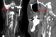

• La scansione cerebrale mostra l'arteria ispessita e quindi indebolita

• La lunghezza dell'arteria che si è rotta durante l'incidente

• La scansione cerebrale mostra l'arteria guarita

Dopo essere stata travolta da un'onda in vacanza, per una turista irlandese sono iniziati seri problemi. La donna, 60 anni, ha iniziato a soffrire di mal di testa e dolori al collo, oltre che fastidi alle palpebre e alle pupille. Le scansioni cerebrali hanno mostrato che l'urto dell'onda aveva provocato la rottura di vasi sanguigni e di un'arteria nel collo che porta sangue al cervello. I medici, sbalorditi, hanno pubblicato il racconto in una rivista medica e dichiarando che si trattava del primo caso di questo genere. Alla paziente è stata diagnosticata la rara condizione della sindrome di Horner, secondo il racconto pubblicato su BMJ Case Reports. Una condizione causata da danni ai nervi del viso e risultati nella bulbo oculare che affonda nella sua cavità. All'ospedale della Galway University, i medici hanno scoperto che gli occhi della paziente si muovevano involontariamente, ma era comunque in buona salute. Dopo aver assunto inizialmente l'aspirina per evitare l'ictus, la paziente è pienamente guarita sei mesi dopo.